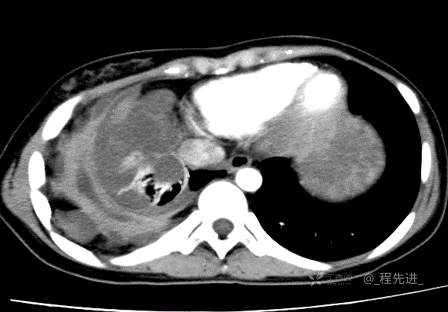

患者性别:女

患者年龄:26岁

简要病史:反复胸闷、气喘、咳嗽半年